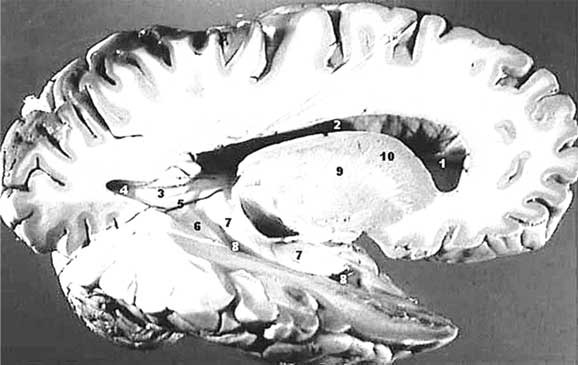

Иллюстрация к книге — Твоя жизнь до рождения: тайны эволюции человека [i_049.jpg]

Серое и белое вещества коры больших полушарий

Но если есть развитая нервная система, то должны быть и эмоции, не так ли? Вопрос о том, какие эмоции может испытывать тринадцатинедельный плод, довольно спорный, но давайте допустим, что он их все же испытывает и выражает свои переживания гримасами и движениями. Кора головного мозга уже сформировалась и что с того, если она пока еще гладкая, без извилин? Борозды, «нарезающие» кору головного мозга на извилины, увеличивают ее площадь, то есть – повышают количество нервных клеток, которые располагаются строго на периферии, тонким слоем. Толщина этого слоя, называемого «серым веществом» за свой цвет, колеблется на разных участках от полутора до четырех миллиметров. Под серым веществом лежит массивный пласт белого вещества, образованного волокнами нервных клеток. Белое вещество не генерирует нервных импульсов, оно их только проводит.

Почему бы природа вместо того, чтобы нарезать в коре борозды, не увеличила толщину серого вещества? Проводящая система могла бы быть и покороче, от этого ничего бы не изменилось. Но, видимо, есть какие-то, пока еще неведомые нам причины, по которым нервным клеткам нужно располагаться в коре тонким слоем. Вот и приходится идти на ухищрения, чтобы увеличить площадь поверхности коры втрое. Неплохой, надо сказать результат. Таким образом, пока кора больших полушарий остается гладкой, высшая нервная деятельность, та самая, которая делает нас разумными созданиями [28], осуществляется в треть своей мощности, но для начала и этого достаточно. Кстати говоря, значение имеет не только количество нервных клеток в коре головного мозга, но и количество связей между ними. Чем больше связей образуют клетки, тем выше функциональные возможности коры.